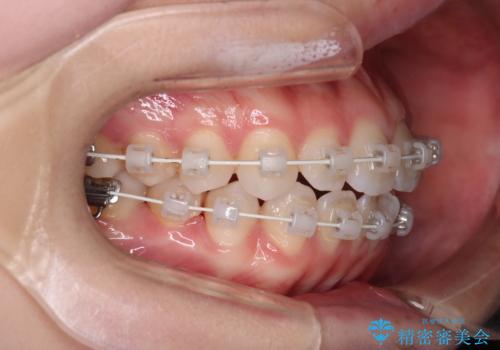

【審美装置】前歯で噛めない!抜歯しないで治したい

- 前歯の捻転とかみ合わせを主訴に来院されました。今回は抜歯をせずにIPRを実施し、並べる計画を立てました。

ワイヤー矯正を行いながら、顎間ゴムを患者さまにご協力していただき、短い期間で終了できました。